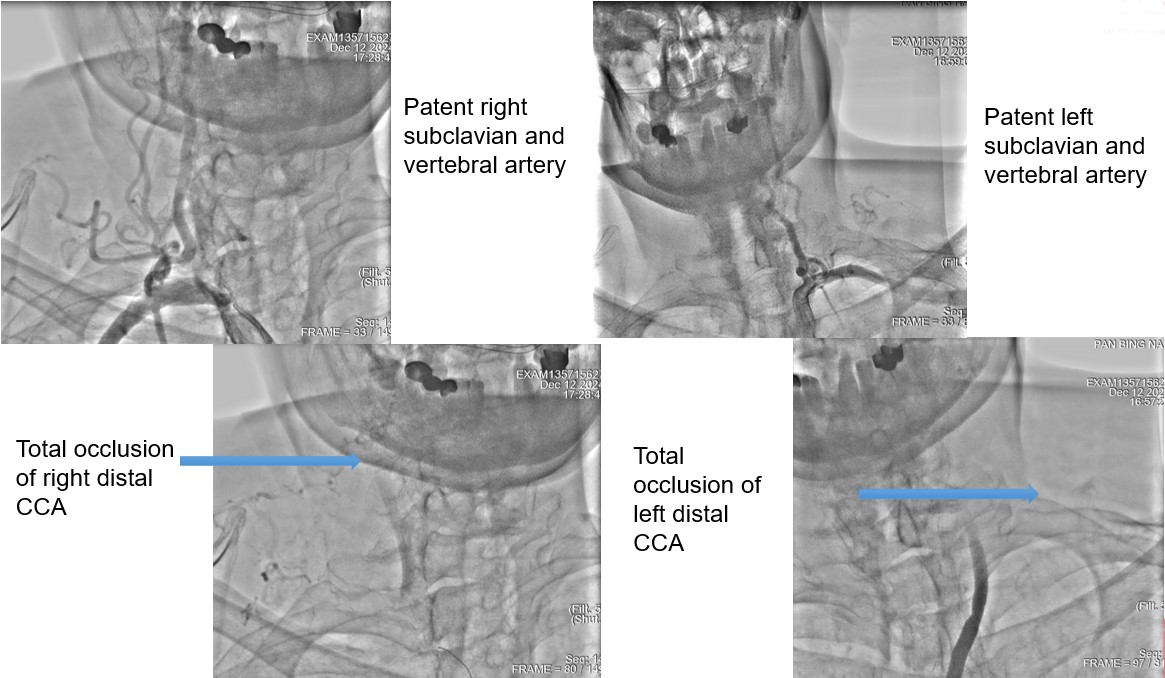

MRI revealed invisible of bilateral ICA, angiography showed bilateral CCA total occlusion with bridge collaterals.ABI showed severe decreased over both sides

Carotid angiography showed bilateral CCA occlusion with bridge collaterals from vertebral and subclavian artery. Patient refused surgical endarterectomy. Lower limbs angiography revealed right SFA CTO, left SFA distal stenosis.We tried endovascular treatment for left CCA occlusion first but failed.

We tried wiring to left ICA occlusion with microcatheter first but failed.Then we tried PTA for right CCA occlusion. With microcatheter support, Gaia 2nd wire advanced to right ICA difficultly2.0mm small balloon pre-dilateddistal filter placement then carotid stenting smoothly.Patient symptoms improved dramatically and discharged 4 days later.We tried elective PTA for right SFA CTO by bilateral puncture approach. Antegrade from left transfemoral cross over sheath, and retrograde from right POPA.Antegrade failed wiringThen retrograde wire successfully advance to antegrade microcatheter -> Rendezvous -> externalization -> balloon pre-dilate and stenting